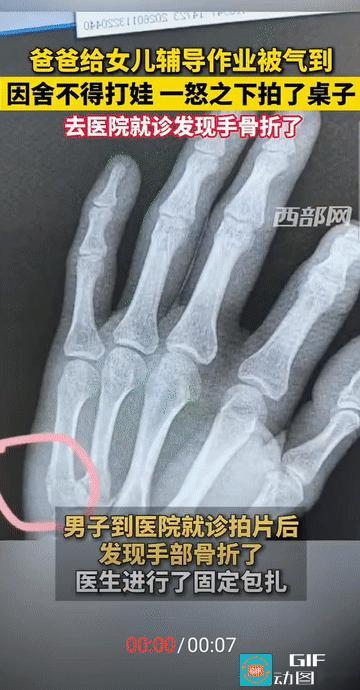

“辅导作业果然是家长的酷刑!”山东,爸爸在家辅导女儿写作业,看着作业本上半小时才挤出的18个字,火气一下上头实在忍不住,但又不舍得打女儿,只得手掌狠狠拍在桌子上,结果桌子完好无损,自己的手却打上了石膏!网友:辅导作业的尽头是骨科! 来源:【大象新闻】 这位父亲像往常一样下班后辅导孩子写作业。明明很简单的一件事,可每天就像是打战一样,本来以为习惯了,谁知看到孩子半小时只写了18个字,作业进展缓慢让,还是让他越来越焦躁! “没舍得打孩子,一拳头捶在了桌子上。”孩子妈妈这样描述当时的情景。随着“啪”的一声,钻心的疼痛从手掌传来,医院检查结果显示为右手第5掌骨骨折! 父亲的手掌迅速肿胀,需要立即打石膏固定。躺在病床上的他坦言:“现在想想又后悔又好笑,不该这么冲动。” 家长们情绪失控的背后是多重压力的叠加。工作一整天的父母,晚上还要变身“家庭教师”,疲惫状态下更容易情绪失控! 教育焦虑的传递也不容忽视。在“不能输在起跑线上”的社会氛围中,家长往往将自身焦虑投射到孩子身上! 有家长坦言:“有时候真是忍不住,这一拳是打在桌子上,要是打在孩子身上,麻烦就大了。” 这种情绪爆发后的后怕,反映出父母在爱与焦虑间的挣扎! 有专家建议,当感到愤怒情绪上升时,采用“暂停策略”。可以告诉孩子:“爸爸/妈妈现在需要冷静一下,我们五分钟后再继续。” 离开现场深呼吸,调整状态后再继续辅导,比硬撑到爆发点更为明智! 把大任务拆解为小步骤,每完成一步给予积极反馈,也能减少对抗! 我们要明白辅导作业的终极目的不是完美无错的作业本,而是培养孩子的学习能力与解决问题的信心!